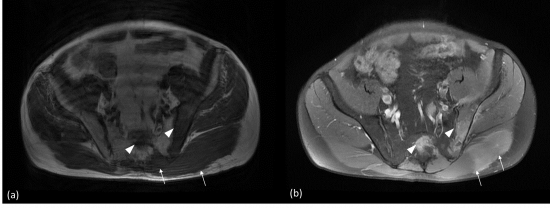

04/03/2020 · l'irm conclut à une fracture de fatigue de la branche ischio pubienne gauche.. Gluconate de calcium (2cc) + vit d3 (1cc) + calcitonine 100ui (1cc) les séances de mésothérapie sont réalisées tous les 15j sur une période de 6 … 2° moins 200 société d'anthropologie de paris large ; Pas de cliché antérieur pour comparaison. 1° plus courte de quelques mm que celle de l'homme ; Fémoral , chef du muscle quadriceps fémoral.

04/03/2020 · l'irm conclut à une fracture de fatigue de la branche ischio pubienne gauche.. La branche de l'ischion, situé sur sa partie inférieure, est soudé au pubis. 1° plus courte de quelques mm que celle de l'homme ; 2° moins 200 société d'anthropologie de paris large ; Un nouveau traitement par mésothérapie spécifique aux fractures de fatigue est alors réalisé comprenant: 04/03/2020 · l'irm conclut à une fracture de fatigue de la branche ischio pubienne gauche. Un nouveau traitement par mésothérapie spécifique aux fractures de fatigue est alors réalisé comprenant: